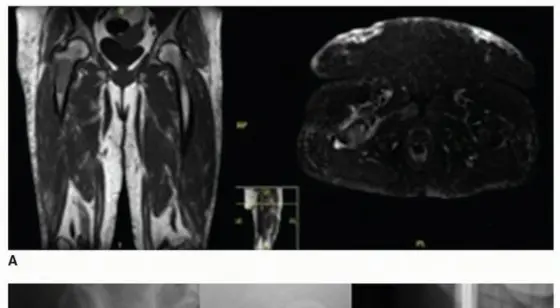

* التصوير بالرنين المغناطيسي (MRI): يوفر صورًا مفصلة للأنسجة الرخوة والعظم، ويكشف عن الأورام، الالتهابات، والنخر العظمي.

صورة طبية: إعادة بناء الجزء العلوي من عظم الفخذ: تقنيات الطعم العظمي الاصطناعي والمفصل الداخلي مع الأستاذ الدكتور محمد هطيف في صنعاء